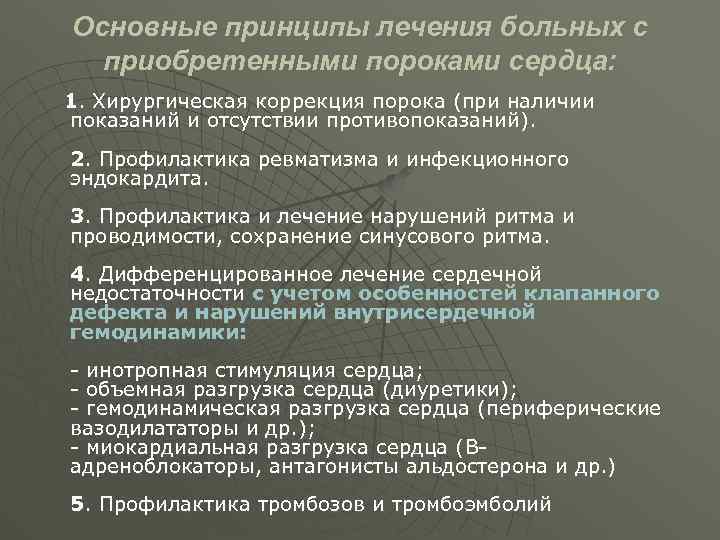

Фотографии и информация о приобретенных пороках сердца